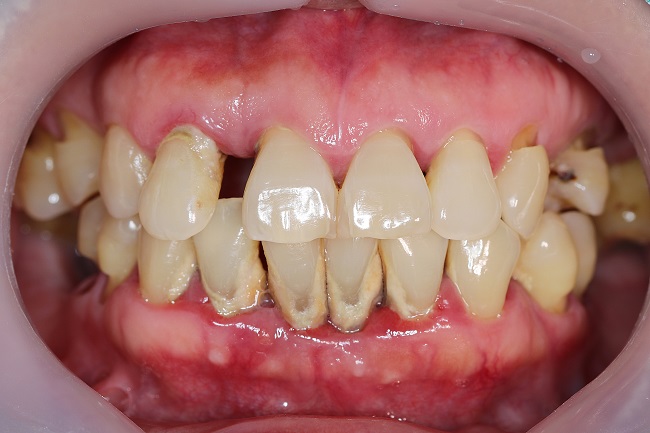

많이 쌓여있는 치석 예시사진

출처: 구글검색

위 예시사진을 보시면 아랫니의 치아와 잇몸 사이에 많은 양의 치석이 쌓여있는 것을 확인하실 수 있는데요.

만약 이 치석이 스케일링을 통해 제거된다면 치아를 잡아주고 있던 치석이 사라지면서 치아가 흔들리는 것처럼 충분히 느껴질 수 있겠죠?

만약 이런 증상이 일시적으로 끝나는 것이 아니라 지속적으로 느껴진다면 다시 한번 치과에 내원하셔서 체크해보시는 것이 좋습니다.